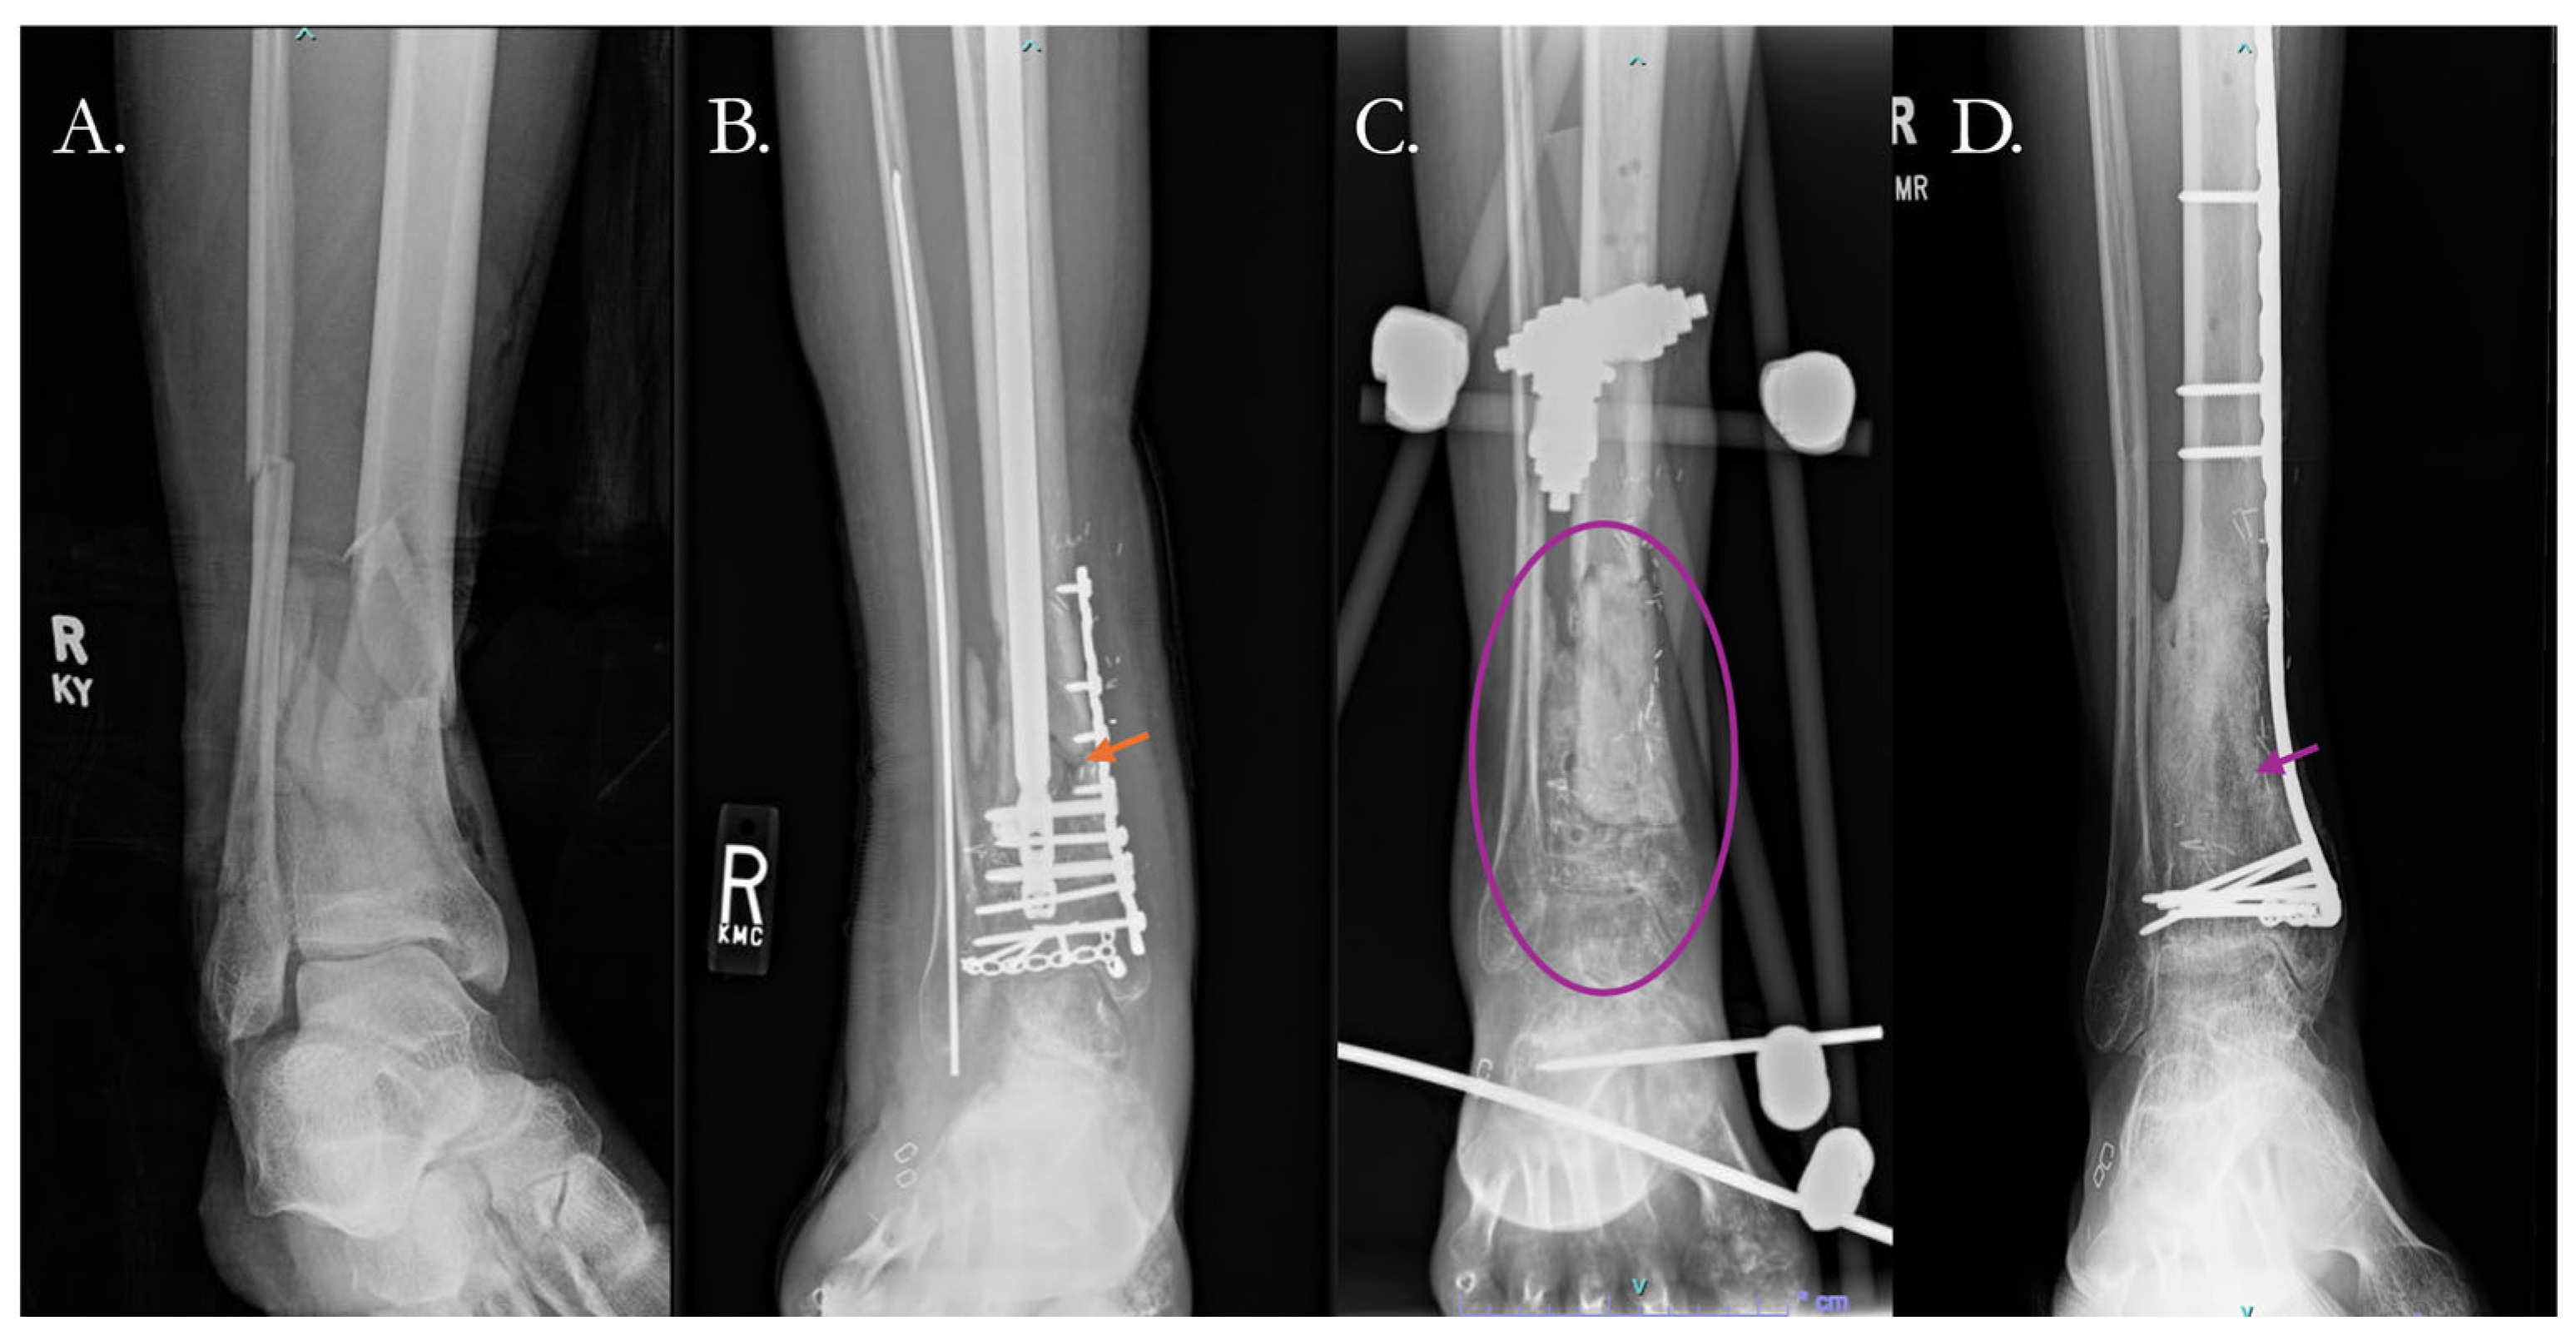

- Chloros, G.D.; Kanakaris, N.K.; Harwood, P.J.; Giannoudis, P.V. Induced Membrane Technique for Acute Bone Loss and Nonunion Management of the Tibia. OTA Int. 2022, 5, e170. [Google Scholar] [CrossRef]

- Griffin, J.T.; Landy, D.C.; Sneed, C.R.; Liu, B.; Kavolus, M.; Pectol, R.W.; Gitajn, I.L.; Oh, J.-K.; Aneja, A. Masquelet Technique for the Tibia: A Systematic Review and Meta-Analysis of Contemporary Outcomes. J. Orthop. Trauma 2023, 37, e36–e44. [Google Scholar] [CrossRef]